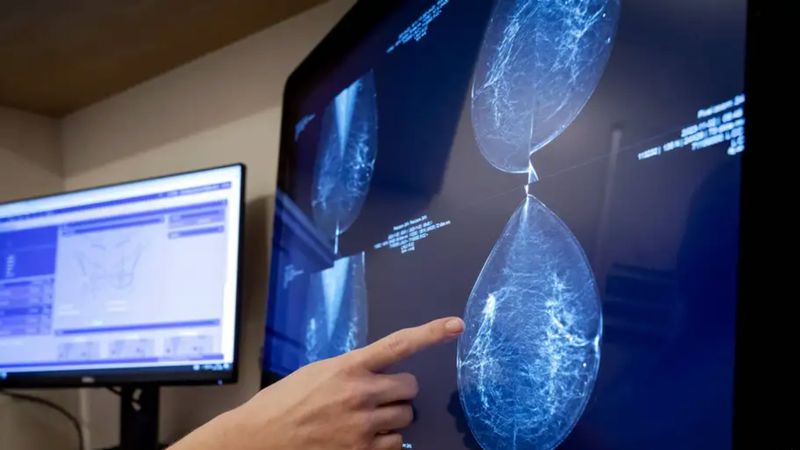

Meme kanseri taramasında devrim yapabilecek bir algoritma sayesinde yeni bir yapay zeka modeli, kişinin 5 yıla kadarki sürede meme kanserine yakalanma riskini başarılı şekilde ölçebiliyor.

Kanser belirtisi göstermeyen, doktorlara göre tamamen normal olan mamografi görüntülerini inceleyen model, gelecek 5 yıl için ayrıntılı bir risk ölçütü ortaya koyabiliyor.